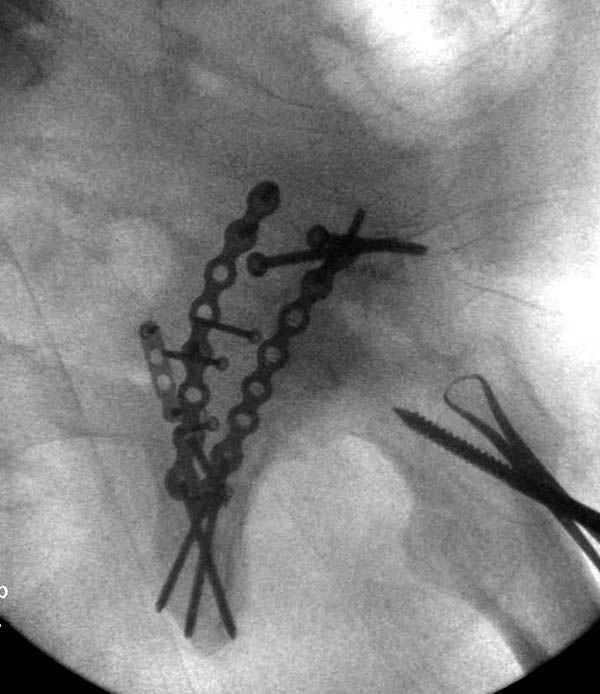

Имя     : 5 Proximal hum+acetabulum CRM.jpg

Url     : http://weborto.net:8080/pipermail/ortho/attachments/20071130/be03ce6b/attachment-0007.jpg